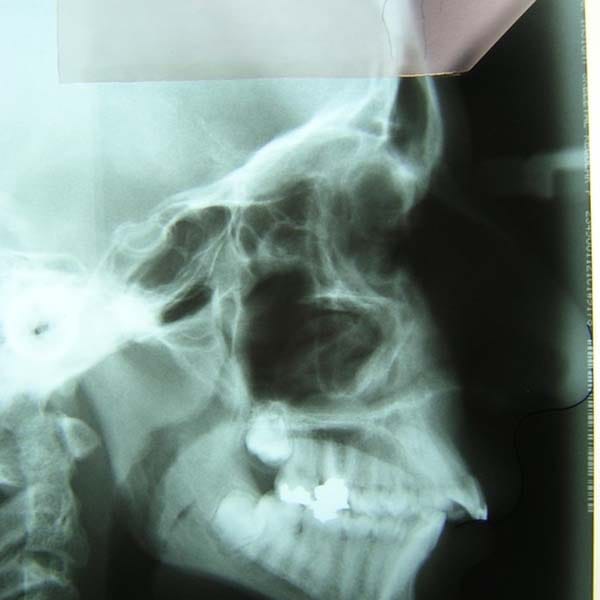

عندما يكون سبب بروز الأسنان هو تراجع الفك السفلي، فإن الحل الأمثل هو التدخل المبكر. بصفتي أخصائي تقويم أسنان في العين، أستخدم الأجهزة الوظيفية لتوجيه النمو. هذه الحالة توضح كيفية علاج بروز الأسنان بالجهاز الوظيفي بنجاح وتأثيره الرائع على ملامح الوجه.

عانى هذا الشاب اليافع من بروز شديد في الأسنان وصل إلى 1 سم، وكان سببه الرئيسي هو تراجع الفك السفلي، وهو ما كان يظهر بوضوح على بروفيل وجهه الجانبي.

كما تظهر الصور، كان التحسن جذرياً ليس فقط في الابتسامة ولكن في تناسق ملامح الوجه بالكامل. تم تصحيح البروز، وتحسنت علاقة الفكين، وحصل الشاب على ابتسامة جميلة وواثقة.